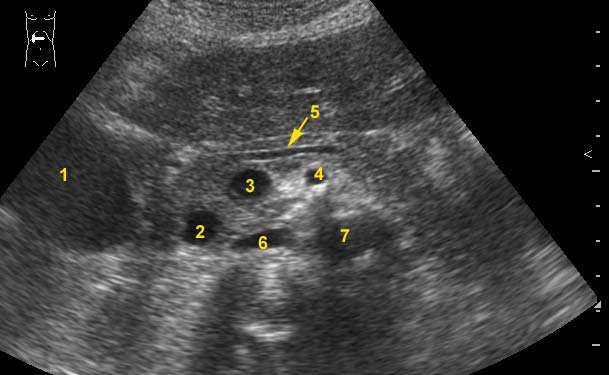

Давайте разберем анатомию.

Перечислите, пожалуйста, отмеченные на сонограмме анатомические структуры.

1- ЖП

2- нижняя полая вена

3-селез.вена

4- верх.брыжеечная артерия

5-вирсунгов проток

6-аорта

7- ?

1- печень

2 - холедох

3- место образования воротной вены

4- ВБА

5 - Вирсунгов проток

6 - НПВ

7 - аорта

Пациент с болевым приступом. Расширен холедох, подраскрыт вирсунгов проток, увеличен желчный пузырь (ориентируемся на сантиметровые метки).